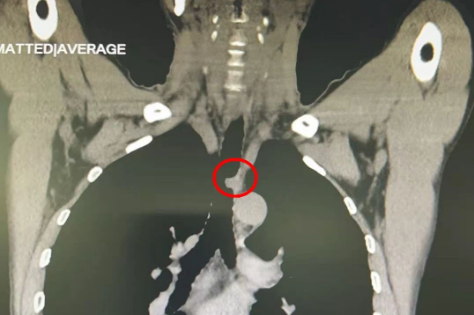

春节刚过,北京天坛医院胸外科主任魏博就在门诊看见了杜先生。由于反复咳嗽,杜先生到老家医院求医,发现气管腔内有肿物,并确诊为气管腺样囊性癌,“找了三家医院,都说做不了这个手术,后来在网上看到天坛医院胸外科有这方面的专家,就赶紧过来了”。“这种肿瘤发病率很低,由于气管的特殊结构,手术难度也比较大。”但杜先生的CT显示,他的气道已经被肿瘤堵塞了一大半,如果再发展下去,有可能危及到他的生命,魏博拍板,马上把杜先生收治入院。